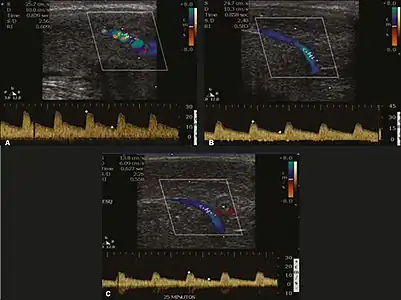

Erection can be induced by injecting 10–20 µg of prostaglandin E1, with evaluations of the arterial flow every five minutes for 25–30 min (see image). The use of prostaglandin E1 is contraindicated in patients with predisposition to priapism (e.g., those with sickle cell anemia), anatomical deformity of the penis, or penile implants. Phentolamine (2 mg) is often added. Visual and tactile stimulation produces better results. Some authors recommend the use of sildenafil by mouth to replace the injectable drugs in cases of contraindications, although the efficacy of such medication is controversial.[39]

Before the injection of the chosen drug, the flow pattern is monophasic, with low systolic velocities and an absence of diastolic flow. After injection, systolic and diastolic peak velocities should increase, decreasing progressively with vein occlusion and becoming negative when the penis becomes rigid (see image below). The reference values vary across studies, ranging from > 25 cm/s to > 35 cm/s. Values above 35 cm/s indicate the absence of arterial disease, values below 25 cm/s indicate arterial insufficiency, and values of 25–35 cm/s are indeterminate because they are less specific (see image below). The data obtained should be correlated with the degree of erection observed. If the peak systolic velocities are normal, the final diastolic velocities should be evaluated, those above 5 cm/s being associated with venogenic ED.[39]

Graphs representing the color Doppler spectrum of the flow pattern of the cavernous arteries during the erection phases. A: Single-phase flow with minimal or absent diastole when the penis is flaccid. B: Increased systolic flow and reverse diastole 25 min after injection of prostaglandin.[39] -

Longitudinal, ventral ultrasound of the penis, with pulsed mode and color Doppler. Flow of the cavernous arteries at 5, 15, and 25 min after prostaglandin injection (A, B, and C, respectively). The cavernous artery flow remains below the expected levels (at least 25–35 cm/s), which indicates ED due to arterial insufficiency.[39]